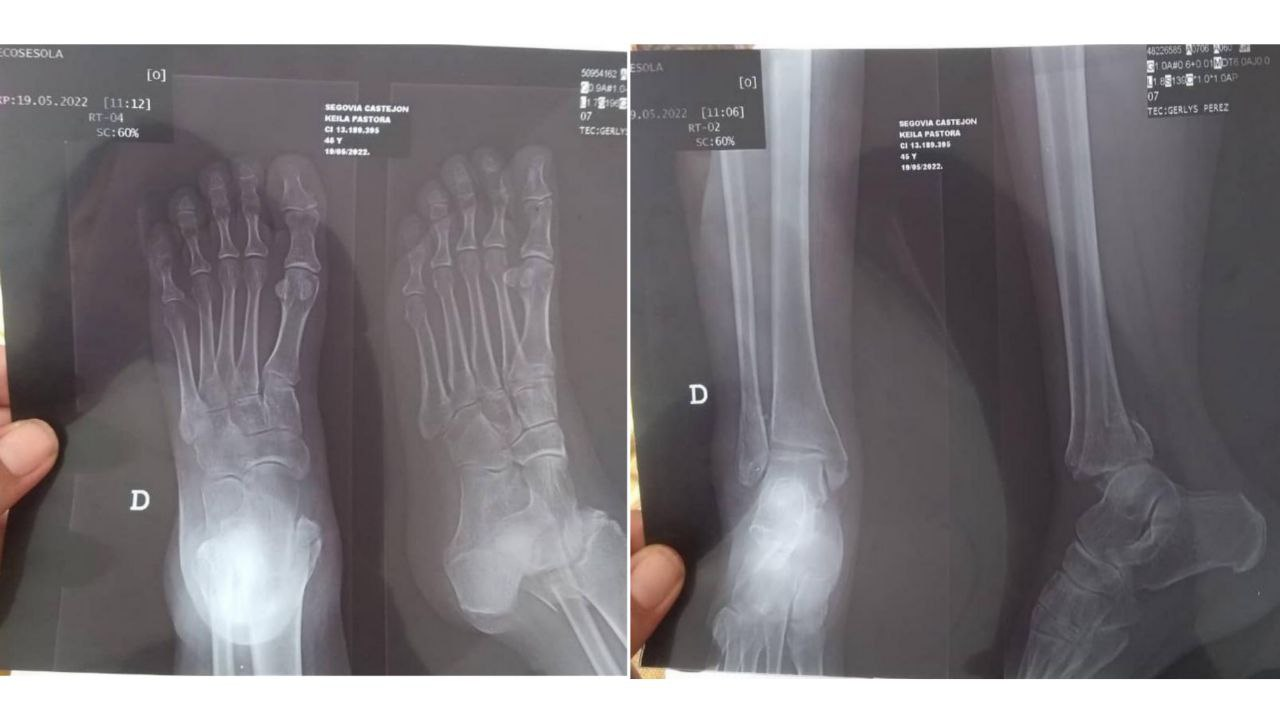

Nuestra amiga Keyla tuvo una caída cerca de su hogar dónde como resultado tiene múltiples fracturas en el tobillo, por lo que amerita una cirugía lo más pronto posible pero no cuenta con los recursos para dicha operacion y para nadie es un secreto que aquí en Venezuela ya no contamos con recursos gratis para un caso como este, y de lograr la cirugia hay que comprar todo lo necesario para ejecutarla(medicinas, kit quirurgico, etc) por lo que estamos recurriendo a ustedes y entre todos poder colaborar en algo para su pronta recuperación, no es fácil lidiar con la situación país y encima con un inconveniente de salud, es terrible algún malestar en nuestro organismo así que no puedo imaginar el gran dolor que siente nuestra amiga en estos momentos.

Estoy adjuntando en esta publicación pruebas convincente de la ayuda que amerita la amiga Keyla también hay usuarios que viven cerca que pudieran corroborar que lo que estoy exponiendo aquí es real y verdadero.

Todas las imágenes son exclusivas para STEEMIT enviadas via whatsapp por @keydoce. picsART